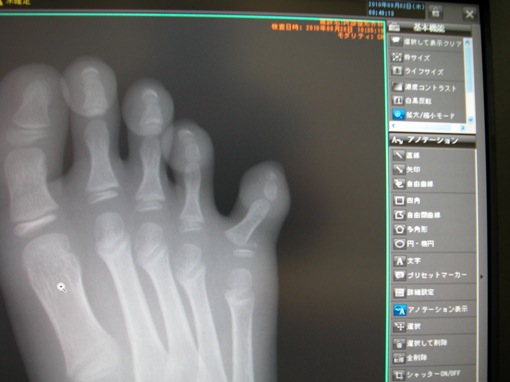

で、息子の足の指なんですが、やっぱり骨折してました。

レントゲンを見れば一目で分かります。